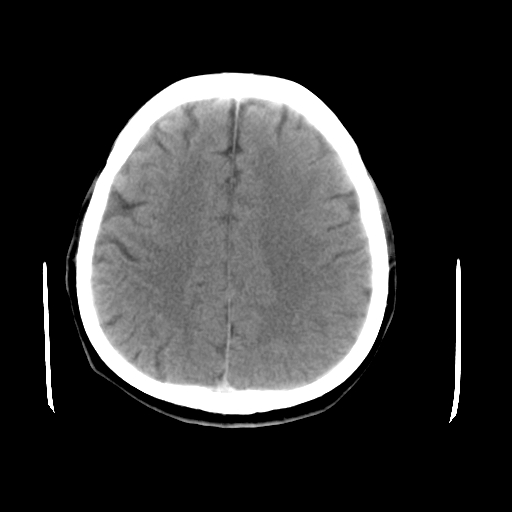

以下是引用liuyue在2008-4-28 13:34:00的发言:[br]右额叶条状高密度影,边缘清楚,周围未见水肿及占位.[br]考虑:血管畸形可能性大.[br]建议:强化ct扫描或mri检查.除外脑回钙化.

以下是引用论黑辩白在2008-4-28 12:53:00的发言:[br]右额叶局限性脑萎缩,右额叶见条状高密度影,建议mri进一步检查。[br][br][本贴已被 论黑辩白 于 2008-4-28 13:08:16 修改过]